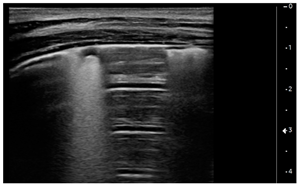

- Vertical artifacts, pleural line indented with several B-lines per field in all regions

![]() | PATTERN 3 Vertical artifacts, pleural line indented with several B-lines per field in all regions |